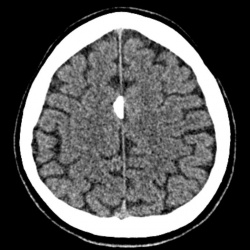

6 мес назад травма ( ДТП), лечился амбулаторно, в течение последнего месяца отмечет усиление головных болей, ососбенно по ночам.